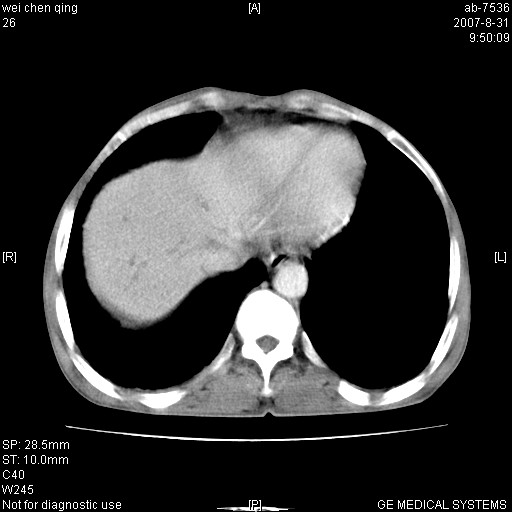

以下是引用zyyzzy在2007-8-31 14:34:00的发言:[br]该病人肝内胆管扩张,胆囊及胆总管未见明显扩张。在倒数第9层图像上可看到左右肝管结合部(肝总管)有软组织影,此处应薄层扫描。考虑肝总管占位(ca)、腹水。[br]